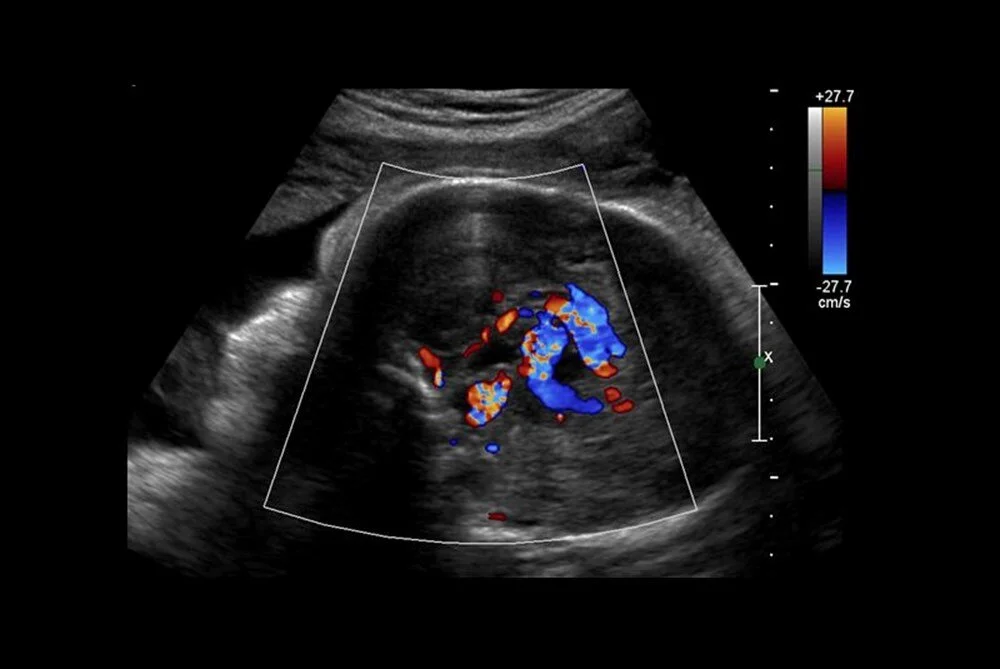

Anneyi 34. haftada ameliyat eden bilim insanları, operasyonu yönlendirmek için ultrason kullandı.

Diğer taraftan, operasyon kapsamında 10 sağlık görevlisinden oluşan bir ekip, annenin karnından uzun bir iğneyi bebeğin beyninin arterlerin etkilendiği kısmına yönlendirmek için ultrason kullandı. Doktorlar, daha sonra damarlara geri akışı engellemek için damar içine küçük bir madde enjekte etti.